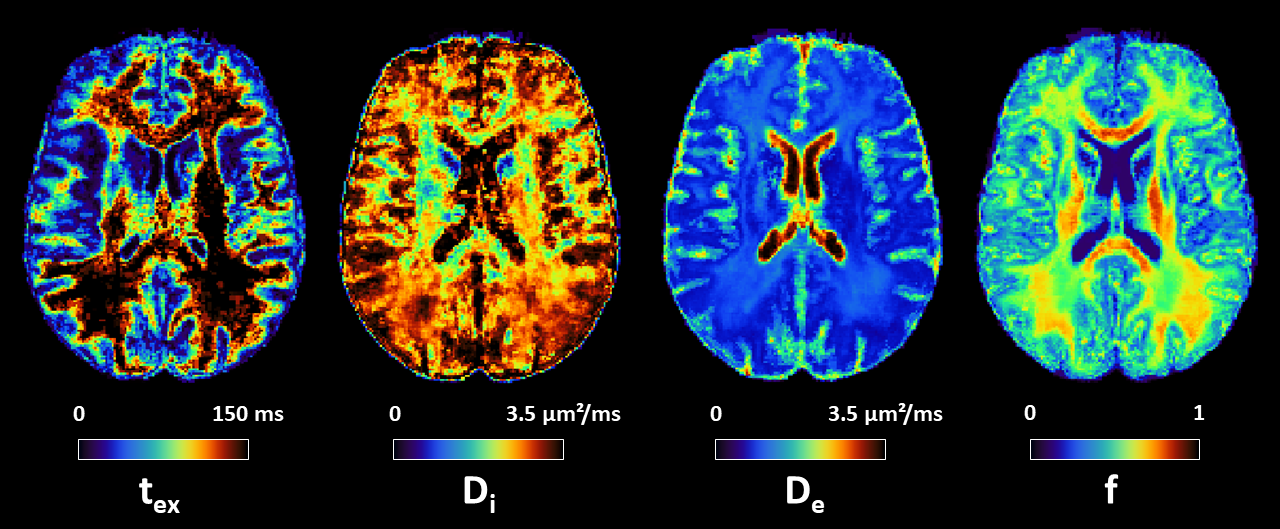

Development and optimization of human gray matter microstructure quantification using diffusion MRI